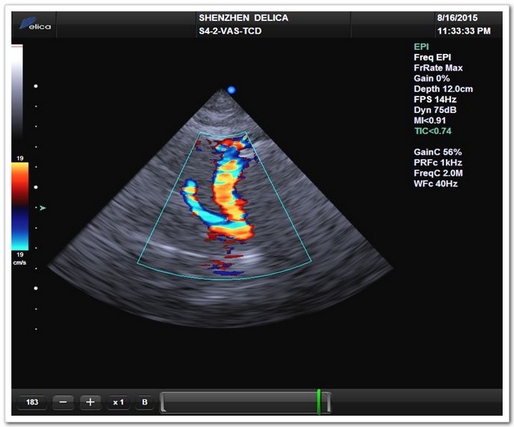

TCD模式(大腦中動(dòng)脈)

TCD模式(頸內(nèi)動(dòng)脈終末段)